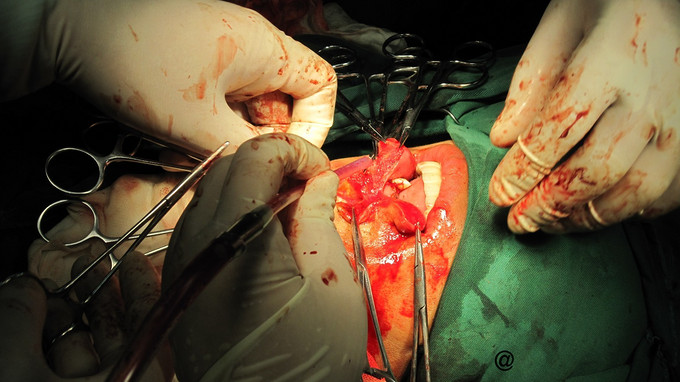

诊断:左下牙龈鳞癌伴左下颌骨、左颈淋巴转移 治疗:入院后行术前常规辅查,T99全身核素扫描结果示左下颌骨放射状性分布浓缩影,结合病史考虑肿瘤左下颌骨转移。于2012年11月20日开始用平阳霉素行术前诱导化疗;并行颈部CT增强扫描考虑有颈部淋巴结转移。12月8日化疗结束平阳总剂量达160mg;肿瘤体积缩小约30%。复查血生化、血气、胸片未见肺纤维化。为尽量达到预期治疗的目的,医生术前与患者及家属进行充分沟通,征得同意后于12月18日在全麻下为患者行'左侧改良性颈淋巴清扫术十左下牙龈癌切除术十左下颌骨阶段切除术十左下颌骨重建钛板连接朮十左胸大肌带肋骨岛状肌皮瓣转移修复术。手术历经约8h,输血800ml,术中并送切缘冰冻报告为阴性,术后于ICU复苏拔管,次日回病房行留置胃管、防感染等综合治疗。

随访:术后二天,见口内皮瓣色泽正常无发黑,术后一W,见皮瓣远端裂开出现约1.0cm长口腔瘘口,经冲洗换药置碘仿沙条数次,并补充白蛋白助瘘口愈合,于术后一月出院转肿瘤科行术后化疗。并分别在三月后,半年,一年,二年,三年进行跟踪回访,未见有肿瘤复发迹象。 讨论:本病例因左颈部淋巴结考虑有转移,假如采用颈部肌皮瓣转移修复缺损区可能不安全;故采用远处肌瓣修复。颈清时切除了左胸锁乳突肌便于给胸大肌通过留下空间,避免两块肌肉重叠造成左颈雍肿。同时拮扎左颈外A以減少术中出血;取肋骨时避免损伤胸膜造成气胸,制取胸大肌岛状肌瓣时注意保留左肩峰动静脉;此乃手术成功的关键。(手术的成功,多谢原四川省肿瘤医院头颈外科陈健超主任的大力协助)